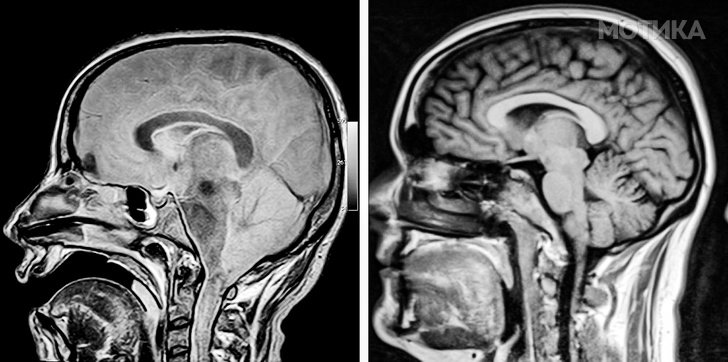

1. Мозокот на пациентот во кома и мозокот на здрава личност